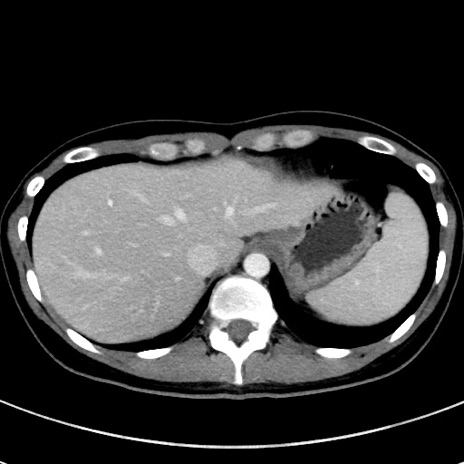

冠状断像

【症例】20歳代女性

【主訴】嘔吐、下腹部痛

【現病歴】昨日夕食後に嘔吐し下腹部痛が出現。本日になっても嘔吐持続し改善しないため来院。

【身体所見】意識清明、BT 37.2℃、BP 108/67mmHg、腹部:平坦、やや硬、下腹部正中から右にかけて圧痛あり、反跳痛軽度あり、tapping pain(+)。

【データ】WBC 13600、CRP 14.94